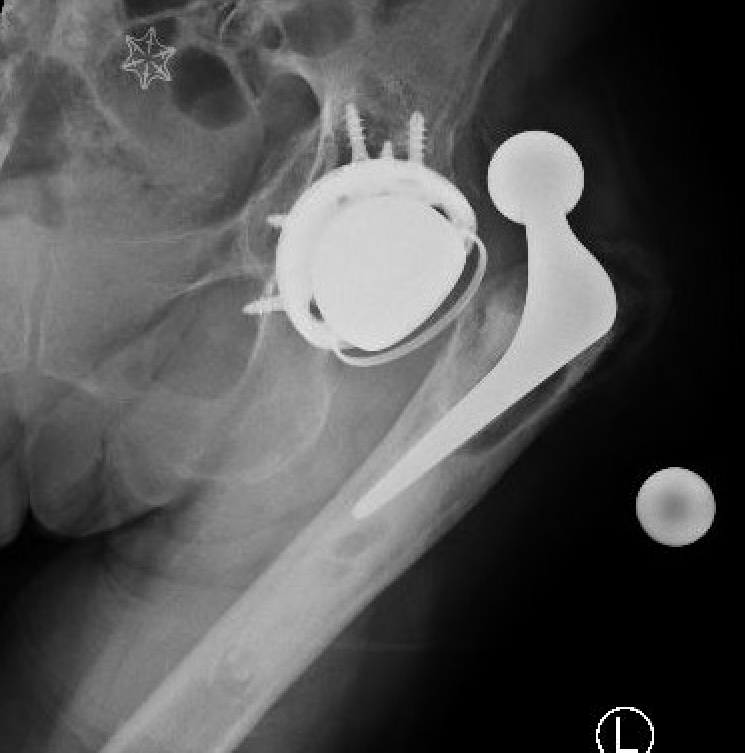

Dislocated constrained liner

Successful reduction constrained liner

Unsuccessful reduction constrained liner